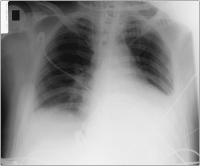

Thoraxröntgen

Abbildung 3: Thoraxröntgen nach Drainage

Kardiologie

Röntgenbild

Thorax